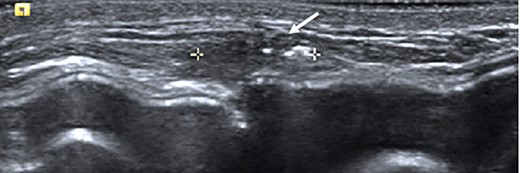

Clinical findings during follow-up were unremarkable until 2020, when she represented with a new lump in the reconstructed left breast neighbouring the mastectomy scar inferiorly. A 1 cm subcutaneous lump with no skin tethering, was palpable along the uniting suture line of the ADM-pectoral muscle. Imaging with ultrasound was indeterminate. This implant proximity rendered it unsuitable for core biopsy due to the high risk of iatrogenic implant perforation (Fig. 2). Subsequent MRI (Fig. 3) illustrated an 11 mm low signal lesion correlating clinically to the palpable lump with mild enhancement but indeterminate appearance.

Ultrasound of the left central breast identified an irregular mass on the capsule of the implant with a focus of hyperechoic calcification (arrow).